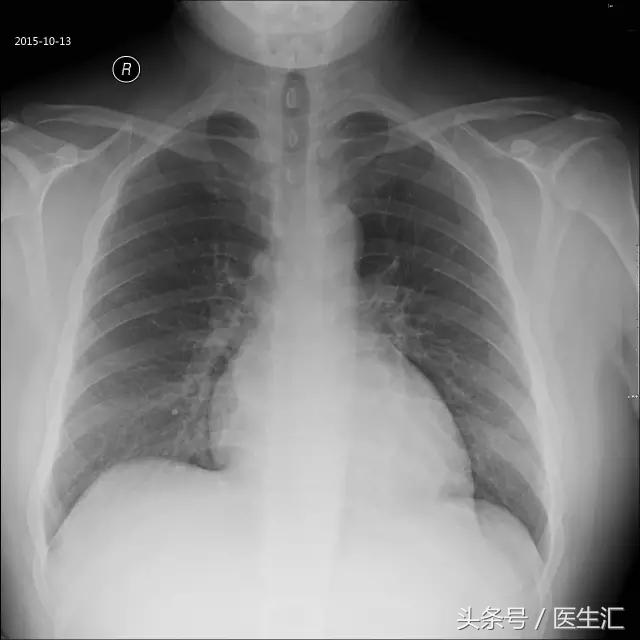

胸片

心影轻度增大(图2)(图3)(2015年10月13日)。